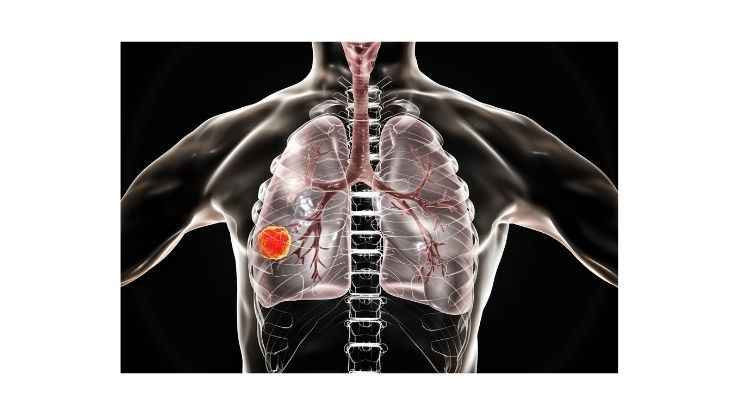

Akciğer kanserinin görünümünün görünümündeki büyümedeki faktörler arasında sigara kullanımı, hava hastalığı , genetik faktörler ve pasif içicilik gibi birçok neden bulunmaktadır. Akciğer kanseri, giderek artan bir tehdit haline gelmektedir. Bu durumun birçok nedeni olsa da, akciğer kanseri riskinin mevcut olduğu ve bu durumun hayati öneme sahip olduğu görülüyor.

Akciğer kanseri, dünya genelinde en sık görülen kanser türlerinden biridir. Kadınlarda erkeklerde olduğu kadar ciddi bir sağlık sorunu da olası değildir. Akciğer kanserinin seyrinde çeşitli faktörler rol oynar, bu faktörler arasında genetik özelliklerin önemli bir yeri vardır.

Kadınlarda akciğer kanseri, son yıllarda hızla artan bir sağlık sorunu haline geldi. Akciğer kanseri, genellikle erkeklerde daha sık görülmekte olup, kapasitesi da giderek artan bir oran belirlenmektedir. Bu nedenle, akciğer kanserinin erken teşhisi için önemli olan virüsler ve virüsler hakkında bilgi sahibi olmak son derece önemlidir. Kadınlarda akciğer kanseri erken teşhisinin önemi, hayatı kurtarıcı olabilir.